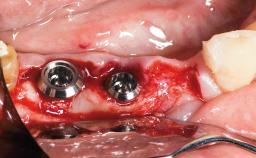

Replacement of a Maxillary Left Second Premolar Using an Immediate Restoration Protocol

In June 2002, a healthy and cooperative 42-year-old female patient was referred for consultation and for the treatment of a fractured maxillary left second premolar. The patient reported an uncomplicated medical history, significant only for seasonal allergies. She had been in the continuous care of a general dental practitioner at the University of Florida College of Dentistry for more than ten years, her recent dental history being restricted to routine operative dentistry and periodontal maintenance. Her plaque control and gingival health was considered for the most part to be excellent, and no intraoral periodontal probing depths exceeded 3 mm. Her esthetic demands were considered moderate to high, and she displayed a high smile line. Intraoral examination revealed a Class I malocclusion, characterized by minor tooth misalignment and midline disharmony, for which orthodontic therapy was recommended and rejected. Her gingival biotype was considered medium to thick.